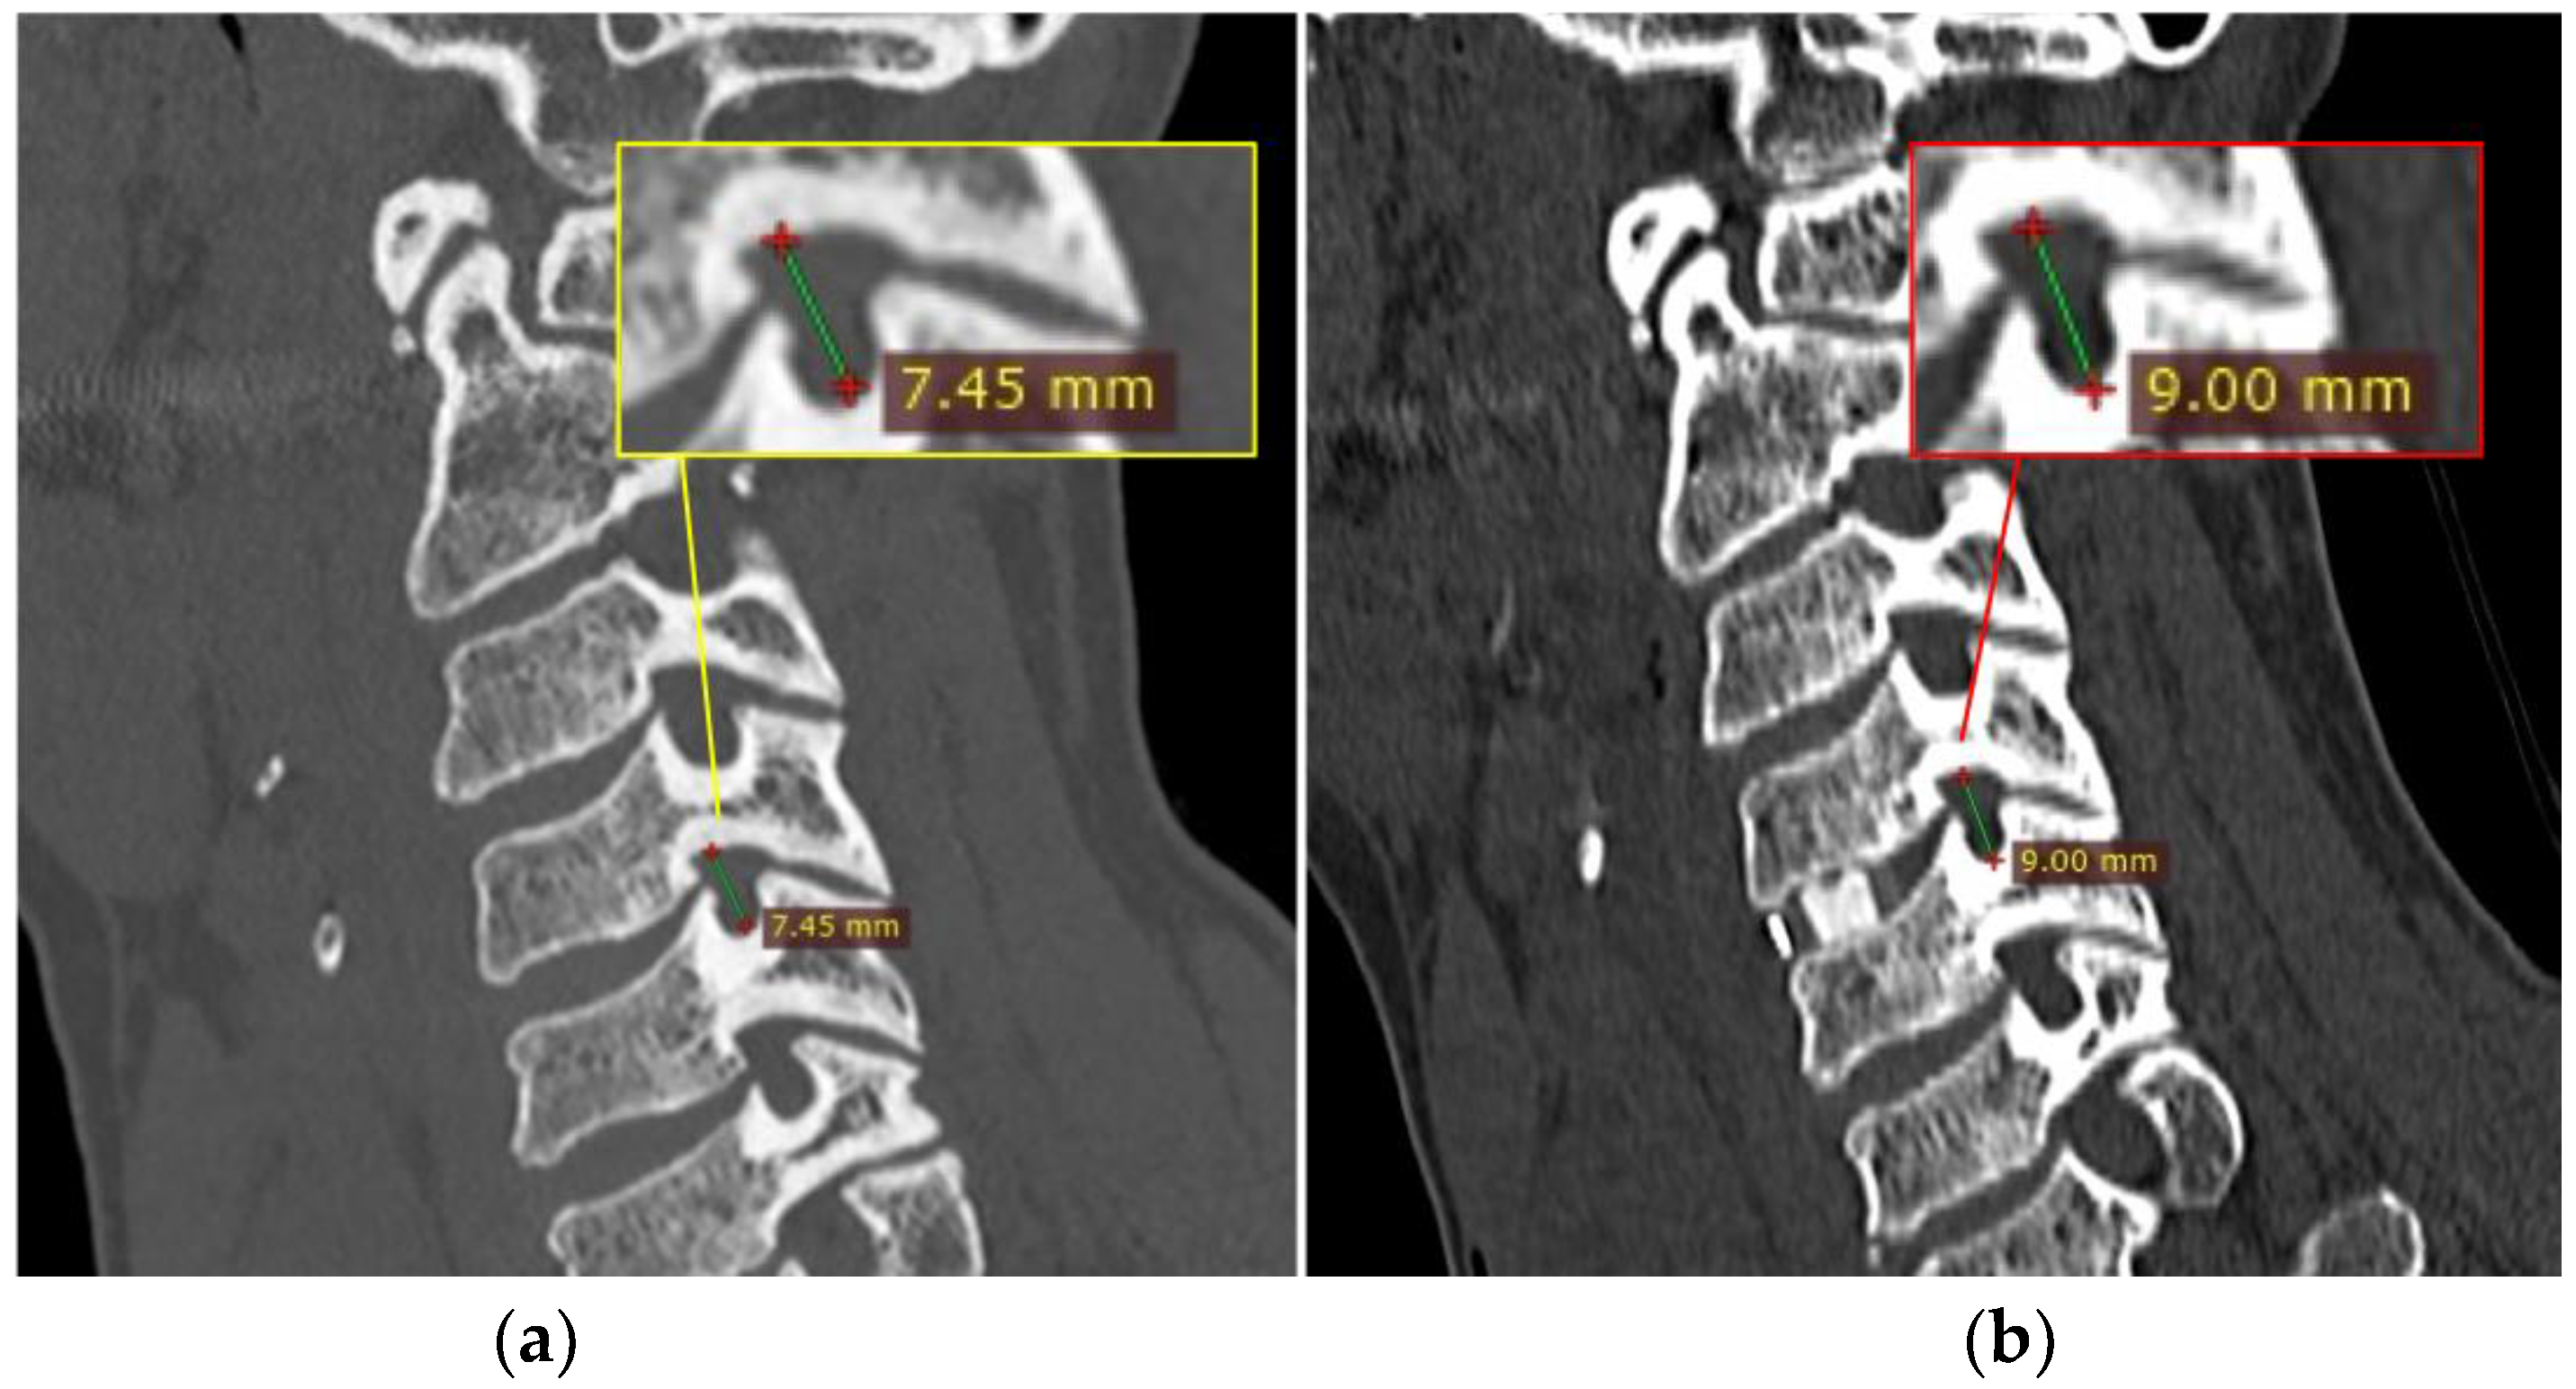

Through the use of MIP and MPR cervical bone-window CT scans, the correct site for measurements at each cervical segment (surgical or above or below) was selected matching the midline point on the anterior surface of the vertebral body on coronal view with the intervertebral foramen plane on axial view, and then adjusted with a plane parallel to the inferior endplate of the level above on the sagittal view. (Figure 1). The antero-posterior (A-P) and cranio-caudal (C-C) diameters of each foramen (surgical and adjacent levels, right and left) were manually measured (Figure 2a). The measurement of the C-C diameter was considered similar to the height of the foramen, and in sagittal reconstruction it was the distance between the midpoint of the upper and lower corresponding pedicles; the measurement of the A-P diameter was considered similar to the width of the foramen, and in sagittal reconstruction it was the distance between the anterior and the posterior border of the inferior intervertebral notch. For the intervertebral disc measurement, the disc height was measured in the anterior, middle, and posterior third on sagittal CT scans. The measure of the intervertebral disc space was considered from the corresponding point (anterior, middle, and posterior) of the inferior endplate of the upper vertebral body to the superior endplate of the lower vertebral body (Figure 2b). CT scans were performed before and within 72 h after surgery, usually the day after the procedure.

Figure 2. In (a) the outline of the foramen is drawn in yellow and in (b) the measurement of the intervertebral foramen antero-posterior (A-P) and cranio-caudal (C-C) diameters are drawn in red, which means foramen width and height, respectively, are shown with red lines. In (c) the red lines show the antero, centrum and postero disc height measurement.